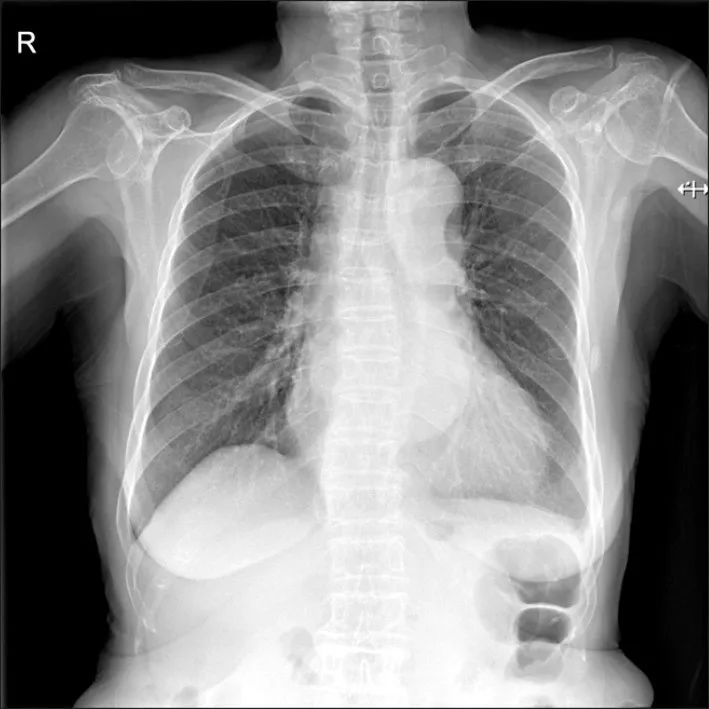

心电图提示:窦性心律,非特异性ST段改变。心肌酶、TnI水平均为正常,D-二聚体升高(13.60 ug/mL),其他实验室检查未见明显异常。急诊医生考虑胸痛原因不太可能是ACS,进行了胸片(图1)及CT检查(图2)。

图1 胸片提示纵膈轻度增宽

图2 CT检查提示A型主动脉夹层(A, B)远端靠近右侧肾动脉主干

没有冠脉介入治疗的指征,立即联系胸外科进行紧急手术。术后患者出现房颤,连续泵入胺碘酮治疗后得以控制。术后18天患者出院,恢复良好。